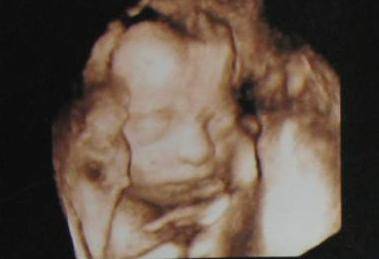

其实以上的两种方法都是猜测的一种,可能几率比其它的大。主要判断男友还是B超,大部分孕妈四个月的时候,孩子的生殖器官就形成了,这个时候如果用三维B超查看性别,那真的很准。为什么不说普通B超呢?因为有时候还在在肚子乱动可能手啊什么的会挡住生殖器,所以用三维就最好的。

B超虽然准确率很高,又有科学根据,可由于一些影响问题,规定不能用B超来查看孩子的性别。